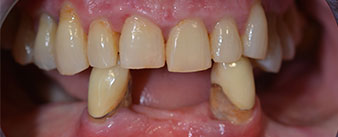

Die 64-jährige Patientin wurde mit einer Unterkiefer-Restbezahnung 38, 33 und 43 und einer klammerbefestigten Interimsprothese im Unterkiefer vorstellig (Abb. 1 und 2).

Die notwendige parodontologische Behandlung und Extraktion im Oberkiefer sollte zu einem späteren Zeitpunkt erfolgen, da die Patientin Lehrerin ist und zu dem Zeitpunkt mit Abiturprüfungen beschäftigt war. Sie konnte weder essen noch adäquat sprechen, da die Interimsprothese sehr häufig und bei der kleinsten Belastung brach.

Nach der Aufklärung über die verschiedenen Möglichkeiten der Versorgung entschied sich die Patientin für eine Extraktion der Restbezahnung im Unterkiefer, eine Sofortimplantation und Versorgung mit der sogenannten Fast & Fixed-Methode (bredent medical). Hierbei wird der provisorische festsitzende Zahnersatz bereits am OP-Tag auf vier Implantaten verschraubt. Das Ziel war, die Patientin am Freitag zu operieren, sodass sie am Montag darauf an den mündlichen Abiturprüfungen teilnehmen konnte.